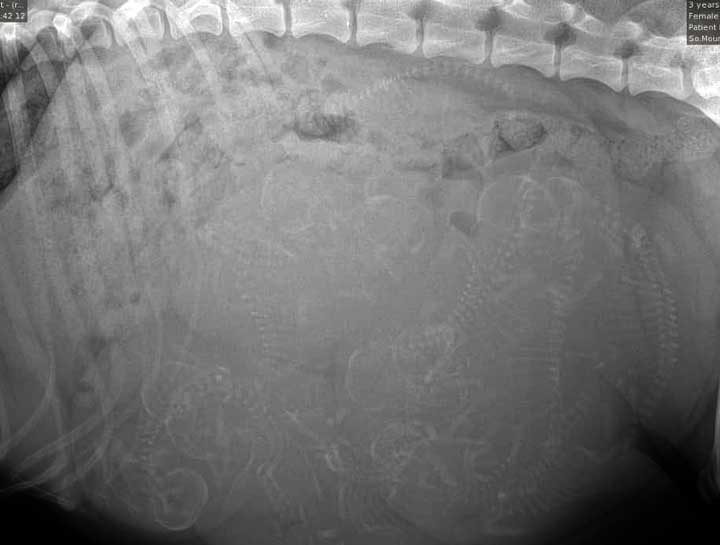

Fetal Digital Radiology

Digital x-rays assist in determining number of fetuses.